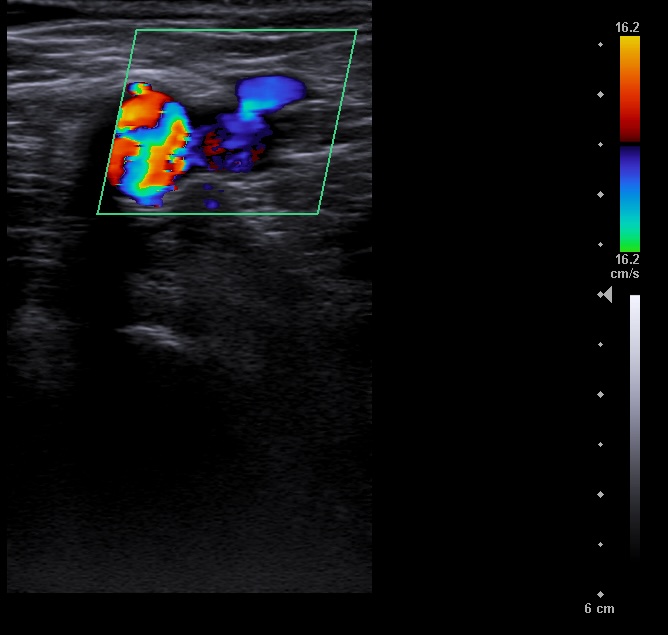

En la ecografía se aprecia vena femoral común, vena femoral superficial, vena safena mayor y vena safena menor con diámetro y flujo normal, llenado total de la luz venosa con el Doppler color y compresibilidad adecuada.

Vena poplitea no compresible, con material ecogénico en su interior y ausencia de flujo con Doppler color.